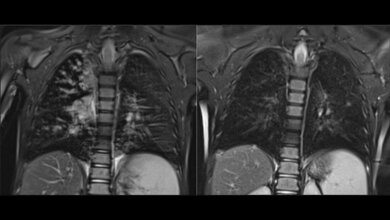

Forschende bemühen sich deswegen, die Vorgänge bei Mukoviszidose noch besser zu verstehen. Eine Studie dazu wurde von einem internationalen Team veröffentlicht. „Wir haben uns speziell damit beschäftigt, wie sich das Immunsystem bei Mukoviszidose verhält, bevor der Kreislauf aus Infektionen und Entzündungen beginnt“, sagt Prof. Nikolai Klymiuk von der TUM. Die Forschenden haben festgestellt, dass in Blutproben von Kindern mit Mukoviszidose und biologischem Material von Schweinen mit dem gleichen Gendefekt bestimmte Zellen des angeborenen Immunsystems unreif sind. Dadurch sind sie weniger effektiv bei der Bekämpfung von Bakterien. Schweine mit Mukoviszidose zeigten zudem schon bei Geburt eine erhöhte Anzahl und eine deutlich veränderte Zusammensetzung von Immunzellen in der Lunge. Die große Ähnlichkeit des Immunsystems von Schweinen mit unserem legt nahe, dass dies bei Menschen genauso ist.

Eine mögliche Erklärung für die Veränderungen des Immunsystems wäre den Autorinnen und Autoren zufolge eine Art „Notfallprogramm“. Dabei wird der Körper angeregt, besonders schnell oder über einen längeren Zeitraum eine große Anzahl von Immunzellen zu produzieren. Eine Folge ist die Bildung unreifer Immunzellen, was zu dem fatalen Kreislauf von Infektionen und Entzündungen bei Mukoviszidose beitragen könnte: Es sind zwar Immunzellen in der Lunge vorhanden, diese sind aber ineffektiv und richten Schaden im Lungengewebe an, ohne langfristig Infektionen zu verhindern. Da in Immunzellen grundsätzlich nur sehr geringe Mengen von CFTR gebildet werden, nimmt das Forschungsteam an, dass der Einfluss von Mukoviszidose auf das Immunsystem indirekt ist. Das könnte erklären, wieso fehlerhafte Immunreaktionen durch die neuartigen CFTR-Modulator-Therapien nicht gut behandelt werden können.